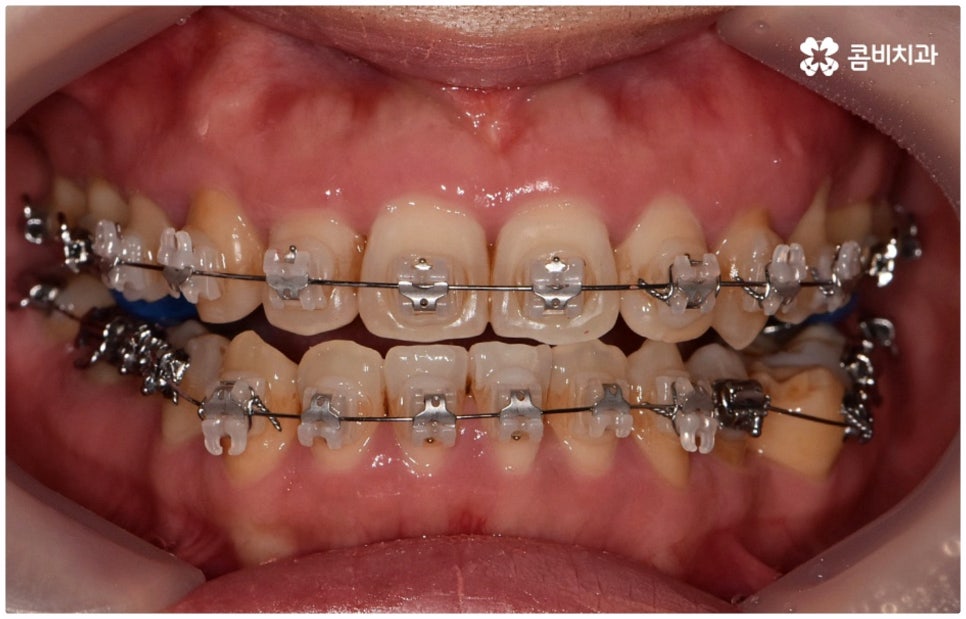

교정 치료가 생물학적 반응을 이용하는 것이다 보니 성장기에 진행하면 치아 이동 및 회복 속도 등에 장점이 있는 것은 분명하지만 그렇다고 해서 성인 이후 중장년 분들이 교정 치료를 받을 수 없는 것은 아니며 이미 많은 분들이 도움을 받고 계신 만큼 이에 대해서 한 번 고려해 보시면 좋을 거예요. 혹시 성장기 이후로는 양악 수술 등으로만 치료가 가능한 것이 아닐까 생각하셔서 부담스럽게 느끼셨던 분들이라면 지레 겁을 먹고 불편함을 그대로 방치하시기 보다는 검진 및 상담을 통해 적극적으로 이를 해결해 보시길 권유드리고 있어요.

물론 원인과 정도에 따라 외과적인 방법이 필요하신 분들도 있을 수 있지만 교정을 통해 얼마든지 치료가 가능한 경우도 있으며 앞서 말씀드렸던 것처럼 발전된 교정 기술 및 특수 미니스크류 등의 장치 개발을 통해 턱의 방향을 조금씩 회전시켜 원거리 치아 이동을 유발하는 것이 가능해졌기 때문에 예전에는 한계가 있었던 부정교합 케이스도 개선될 여지가 늘어나고 있습니다. 꼼꼼하게 검진을 받으시고 자신의 상황에 맞는 교정 치료를 무리하지 않게 진행하신 후 철저하게 사후 관리를 해주시면 보다 오랜 기간 동안 건강하게 고른 치열을 유지하면서 생활하실 수 있을 거예요.